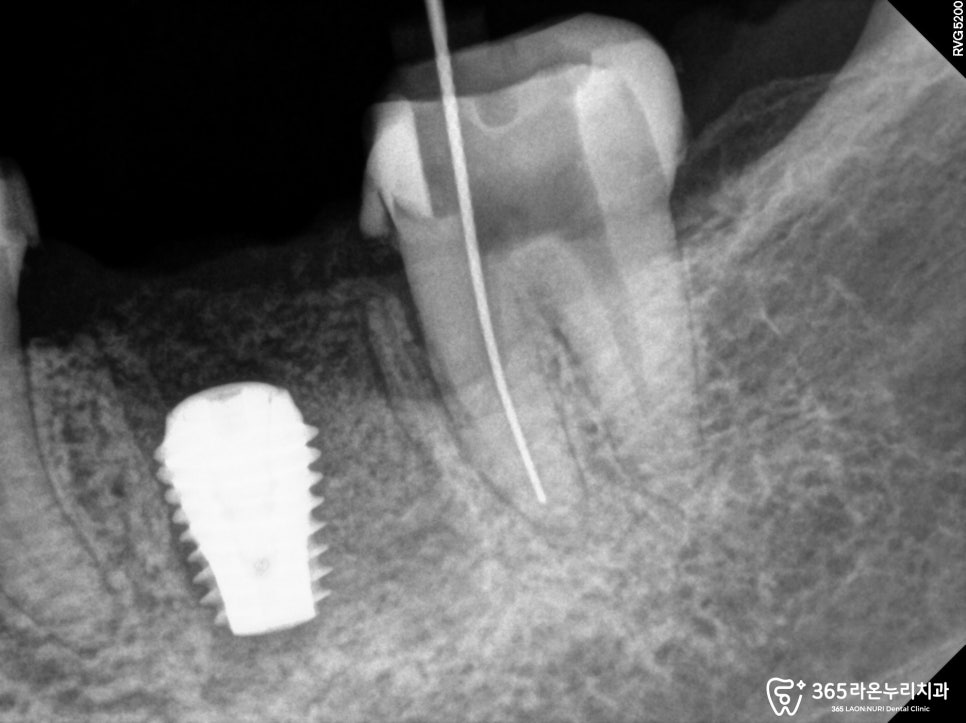

2025.02.13

오산대역 치과 에서

보여드리는 위 사진은

근관속에 있던 신경을

제거하는 과정입니다.